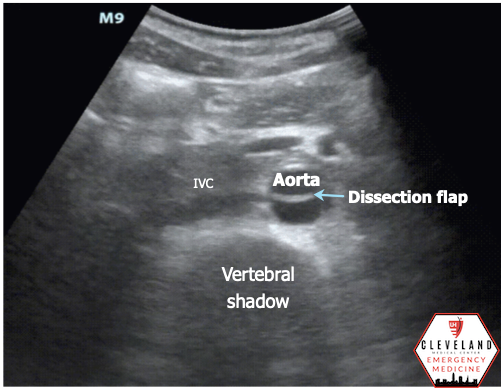

Abdominal aorta transverse view — hyperechoic intimal flap; no apparent aneurysm

Intimal dissection flap within the abdominal aorta. No evidence of aortic root dilation, pericardial effusion, or obvious intimal flat on cardiac views (PSLA shown here). The suprasternal notch view is somewhat limited (you primarily see the descending part of the arch) but there is a thin dissection flap at the branch point of the subclavian artery. Findings are suggestive of aortic dissection.

• Adjust depth to visualize the vertebral body (look for the distinct vertebral shadow) posteriorly with aorta just anterior to this. Don’t confuse more superficial anechoic structures for the aorta.

• Intimal flap — hyperechoic linear flap moving with each pulsation, dividing the lumen into a true and false lumen